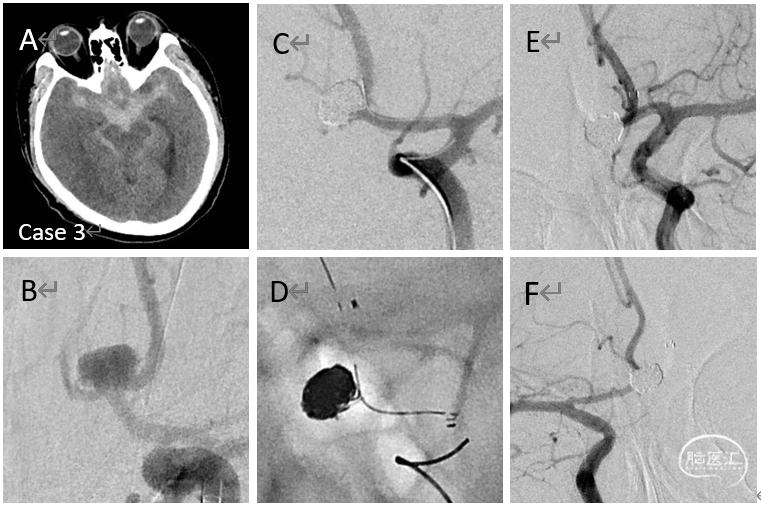

病例3

破裂的前交通动脉瘤支架结合弹簧圈栓塞术(Hunt-Hess 2级,致密栓塞)

病例4-5

破裂的后交通动脉瘤一期单纯栓塞术

(Hunt-Hess 2级)